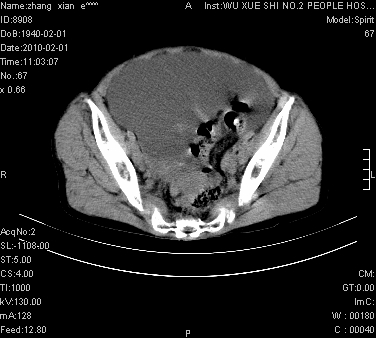

标题: CT24434:70岁 女 腹胀,腹水原因待查 [打印本页]

标题: CT24434:70岁 女 腹胀,腹水原因待查

大量腹水,脾脏囊性占位,子宫颈占位,右侧腹股沟淋巴结肿大,建议+c,先查妇科。

腹盆腔大量积液,子宫增大,子宫颈增大外形不规则,内见低密度影,膀胱后壁显示不清,右腹股沟肿大淋巴结,脾脏囊性占位,子宫颈占位,子宫颈癌?建议增强。

子宫、宫颈占位?转移性腹水?肝性腹水?脾脏囊性占位,囊肿?血管瘤?淋巴瘤?

腹盆腔大量积液,子宫增大,子宫颈增大外形不规则,内见低密度影,膀胱后壁显示不清,右腹股沟肿大淋巴结,脾脏囊性占位,子宫颈占位,子宫颈癌?建议增强。支持!